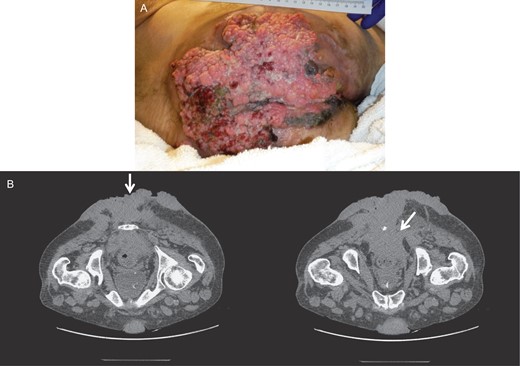

While neoadjuvant chemoradiotherapy, with 5-fluorouracil, mitomycin-C and radiation dose of 45 Gy, at pelvic, perianal and gluteal regions was started, the patient was lost in follow-up. He was readmitted 2 months later for trouble controlling bowels, for which he underwent diverting colostomy. There was significant necrosis of the tumor (Fig. 2), and the biopsy showed with mild to moderate dysplasia. A wide local excision and debridement of the soft tissue were performed down to presacral fascia and gluteal fascia on right and left buttocks.

Gross image (A) and CT of the pelvis and perineum (B) showing exacerbation of the tumor with significant necrosis and invasion into the rectum and anal canal.